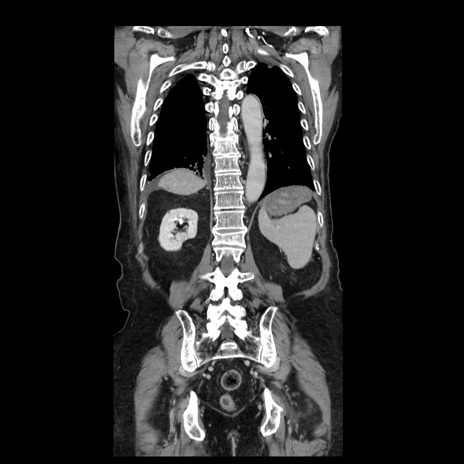

症例21(冠状断像)

【症例】70歳代男性

【主訴】腹痛

【現病歴】肝硬変・肝細胞癌にてかかりつけの方。約9時間前に食後より腹痛出現。症状が徐々に増悪し、嘔吐出現したため来院。

【既往歴】肝硬変、肝細胞癌(RFA、TACE後)

【身体所見】意識清明、表情苦悶様、BT 36℃、BP 129/78mmHg、P 88bpm、SpO2 97%(RA)、右上腹部から心窩部にかけて圧痛あり、反跳痛なし、筋性防御あり。

【データ】WBC 5800、CRP 0.16